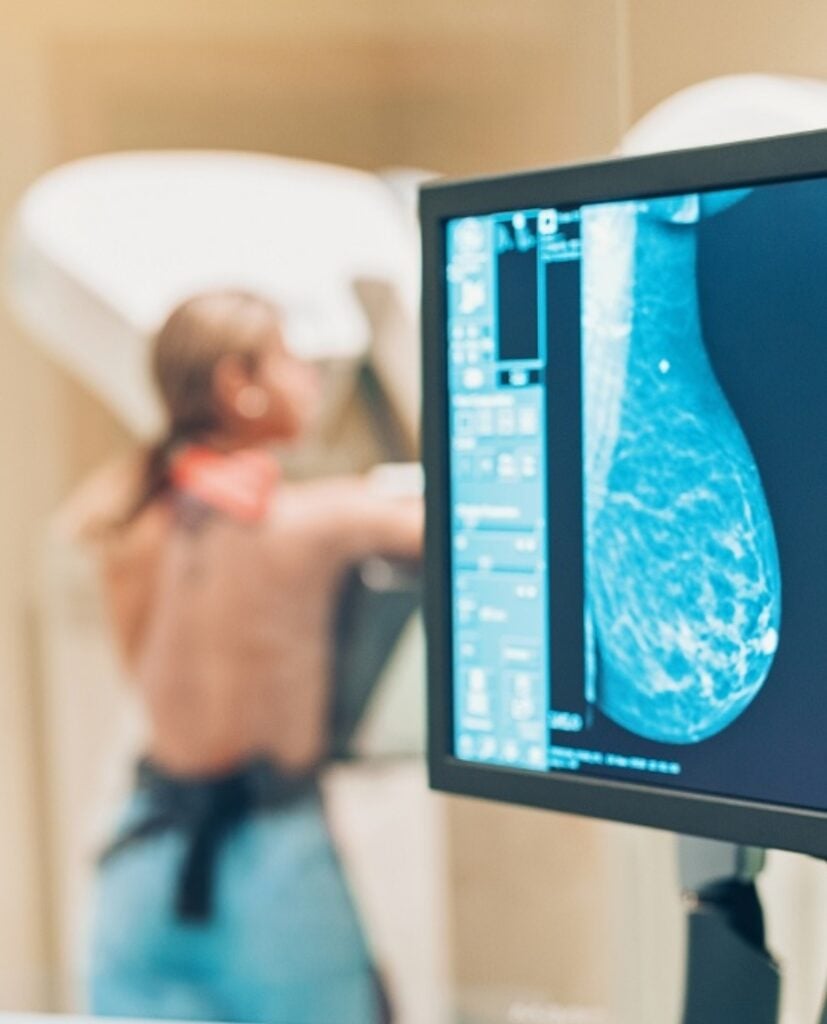

La galena dijo que la mamografía es el estudio más eficaz para detectar el cáncer de mama antes de que se presenten síntomas.

En Cedimat, se cuenta con el mamógrafo GE Pristina, una tecnología de última generación que permite realizar mamografías de alta precisión, biopsias estereotácticas y estudios con medio de contraste.

Este dispositivo, optimizado con inteligencia artificial, ofrece imágenes detalladas que permiten detectar tumores que podrían pasar desapercibidos con métodos tradicionales. Además, permite realizar tomosíntesis o mamografía 3D, una técnica que combina imágenes en 2D con tomografía para una visualización más completa de las mamas.